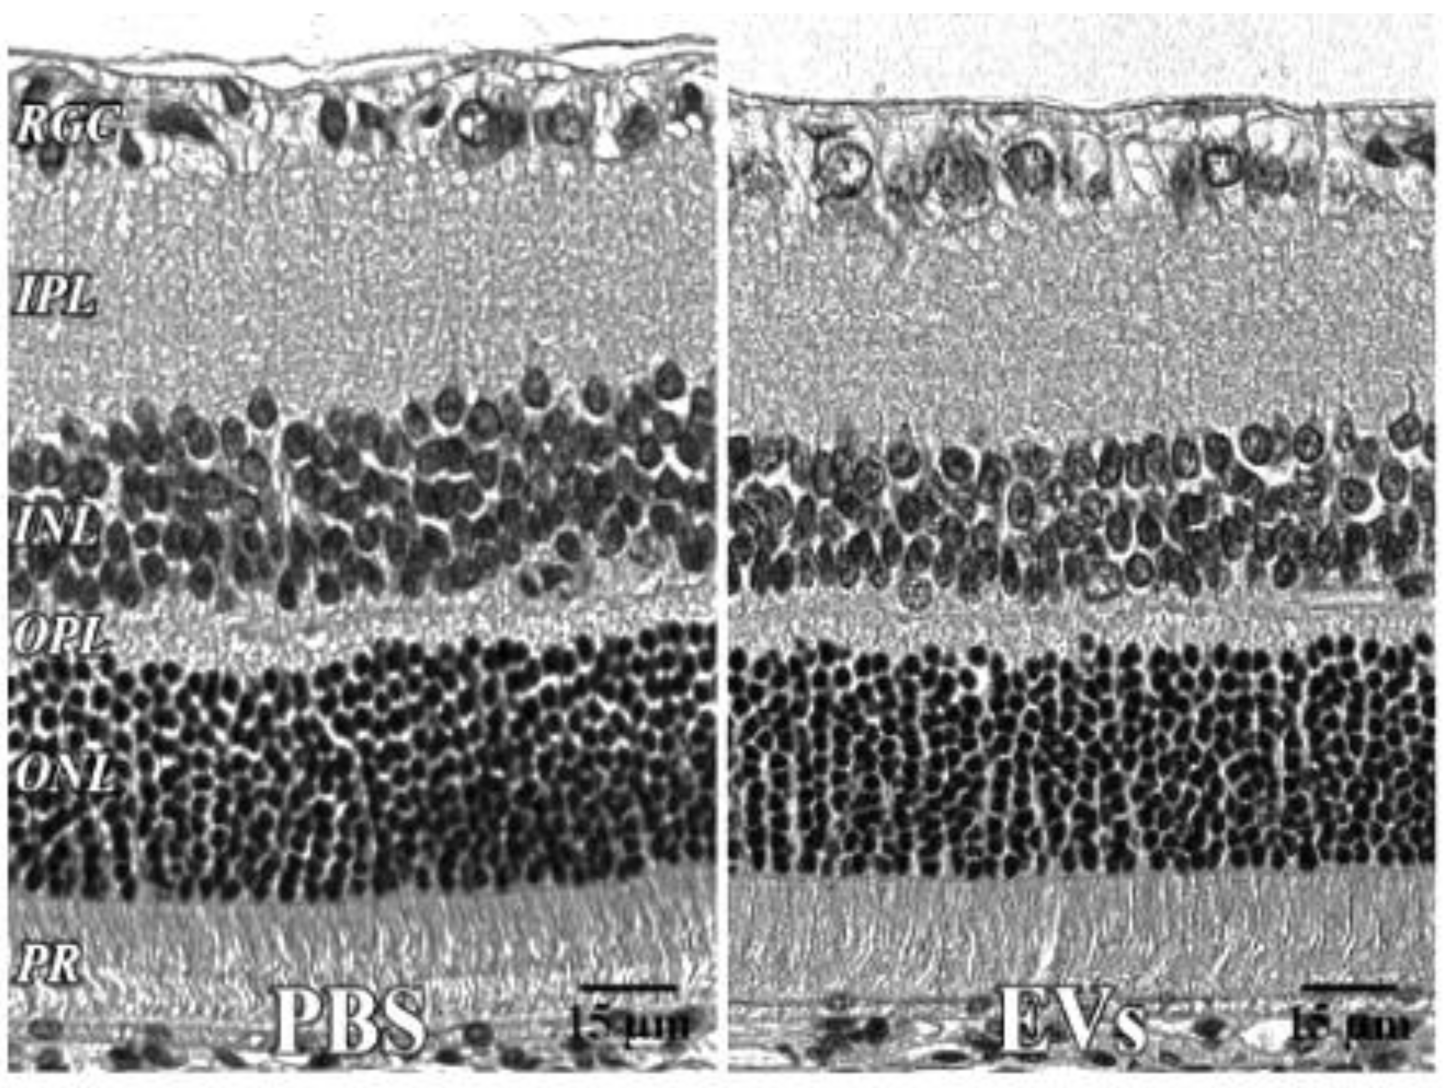

| PBS Eye | EV Eye | ||||

|---|---|---|---|---|---|

| Mean | SEM | Mean | SEM | ||

| Layer | IPL | 44.9 | 2.6 | 42.9 | 0.5 |

| Inner Layer | 102.7 | 5.6 | 101.1 | 0.7 | |

| OPL | 9.9 | 0.4 | 9.5 | 0.7 | |

| Outer Layer | 82.5 | 2.3 | 77.2 | 4.9 | |

| Total | 185.2 | 7.6 | 164.1 | 12.2 | |